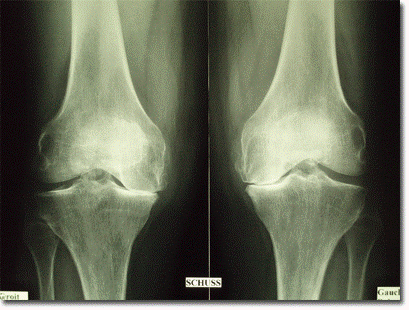

L’arthrose du genou, ou gonarthrose, est l’usure progressive du cartilage, le revêtement lisse qui permet aux os de votre articulation de glisser sans friction. C’est la forme d’arthrose la plus courante.

Avec le temps, ce cartilage s’amincit et peut disparaître. Les os se retrouvent alors en contact direct, ce qui rend le mouvement difficile et douloureux. L’articulation peut se déformer, s’enraidir et limiter votre mobilité. Cette usure est irréversible, mais ses symptômes peuvent être gérés efficacement.